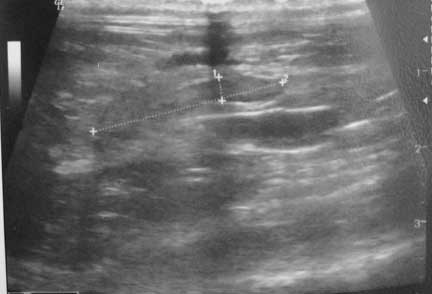

In the other intestinal foreign body case the FB was not seen radiographically and an ultrasound was performed to confirm the diagnosis.

This is the ultrasound. The lines are measuring the size of it in the small intestine.